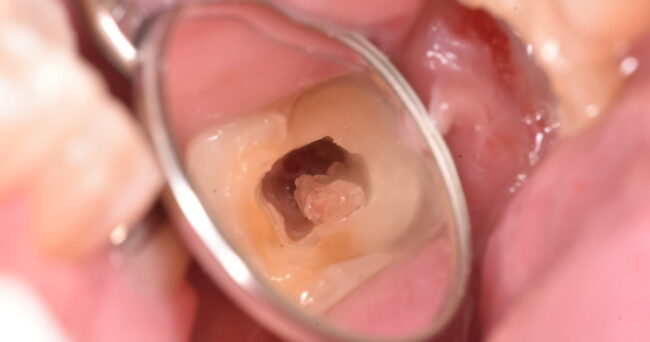

白いものを外した後です。どちらも健全で問題ない歯の色です、と言えるでしょうか?周辺の歯の色と比べてお考え下さい。

また、黒い方ばかりに目が行きがちだと思いますが、色の薄めの方はどうでしょうか?この次の写真とも比べて、よくお考え下さい。

虫歯をあらかた除去した後です。もちろん、↑の写真よりも削った部分は深くなっています。色としてはどちらが明るいでしょうか?

汚染されている部分は、それだけ歯の色が違います。そして、運が悪ければ、最近上げている記事のように、歯の神経が顔を出す結果となります。

加えて、考えていただきたいことがあります。この2本の間の歯茎の状態はどうでしょうか?この状態に対して、白い詰め物をして問題なくつめられるでしょうか?

この状態は、歯の上に歯ぐきがのっかっている状態になります。少なくとも、何か処置をする前にのっかっている歯ぐきを除かなければなりません。除く手段は1.切る2.削る3.焼き切る になります。出血を伴うものと考えていただいて差し支えありません。